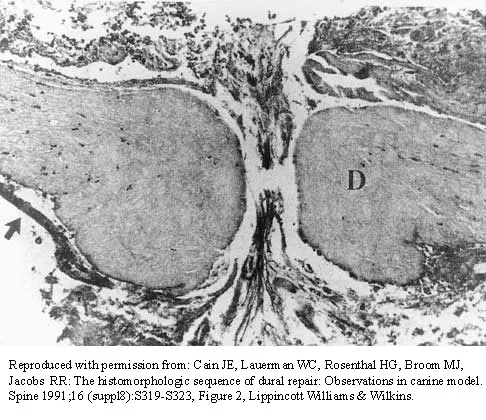

The photomicrograph in Figure 37 shows a repaired dural tear 4 days after surgery. The material interposed between the dural edges (D) is composed of

Explanation